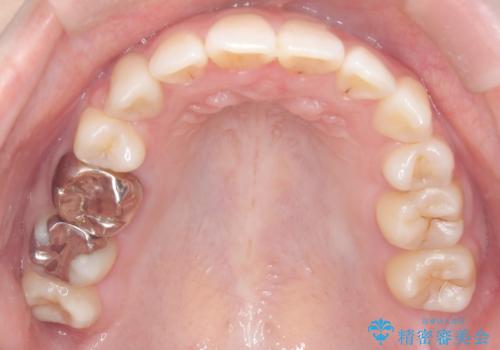

最終的には予定通りインプラントを使用せずに欠損部を閉鎖し、咬合も安定させることができました。